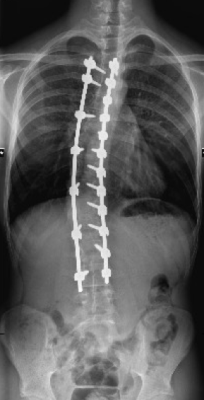

Skoliose

Unter Skoliose versteht man eine dauerhafte Seitverbiegung und Rotation der Wirbelsäule mit gleichzeitiger Verdrehung der Wirbelkörper. Nach ihrer Herkunft lassen sich verschiedene Formen unterscheiden (idiopathisch, kongenital, neuromuskulär, adult), die sich hinsichtlich des Erkrankungsalters, der Ausprägung, des Fortschreitens der Erkrankung und der möglichen Behandlungsverfahren unterscheiden.